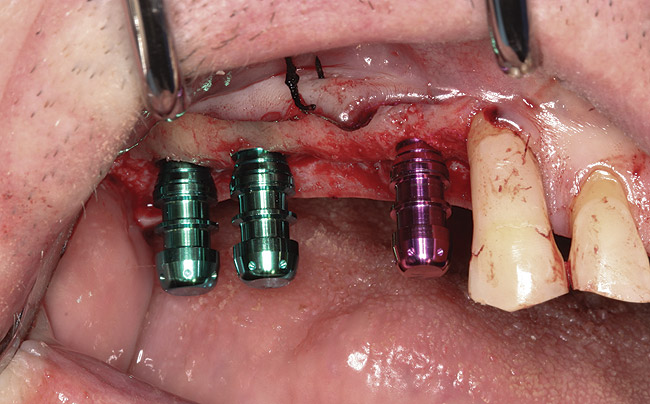

Fig 9. Crestal approach to sinus floor augmentation using special drill system. Osteotomy was carried out with drills in 1-mm-depth increments using depth gauge stoppers, until the intact Schneiderian membrane is visible.

Figure 9

Fig 11. Dental implants are inserted through the crestal osteotomy preparation.

Figure 11